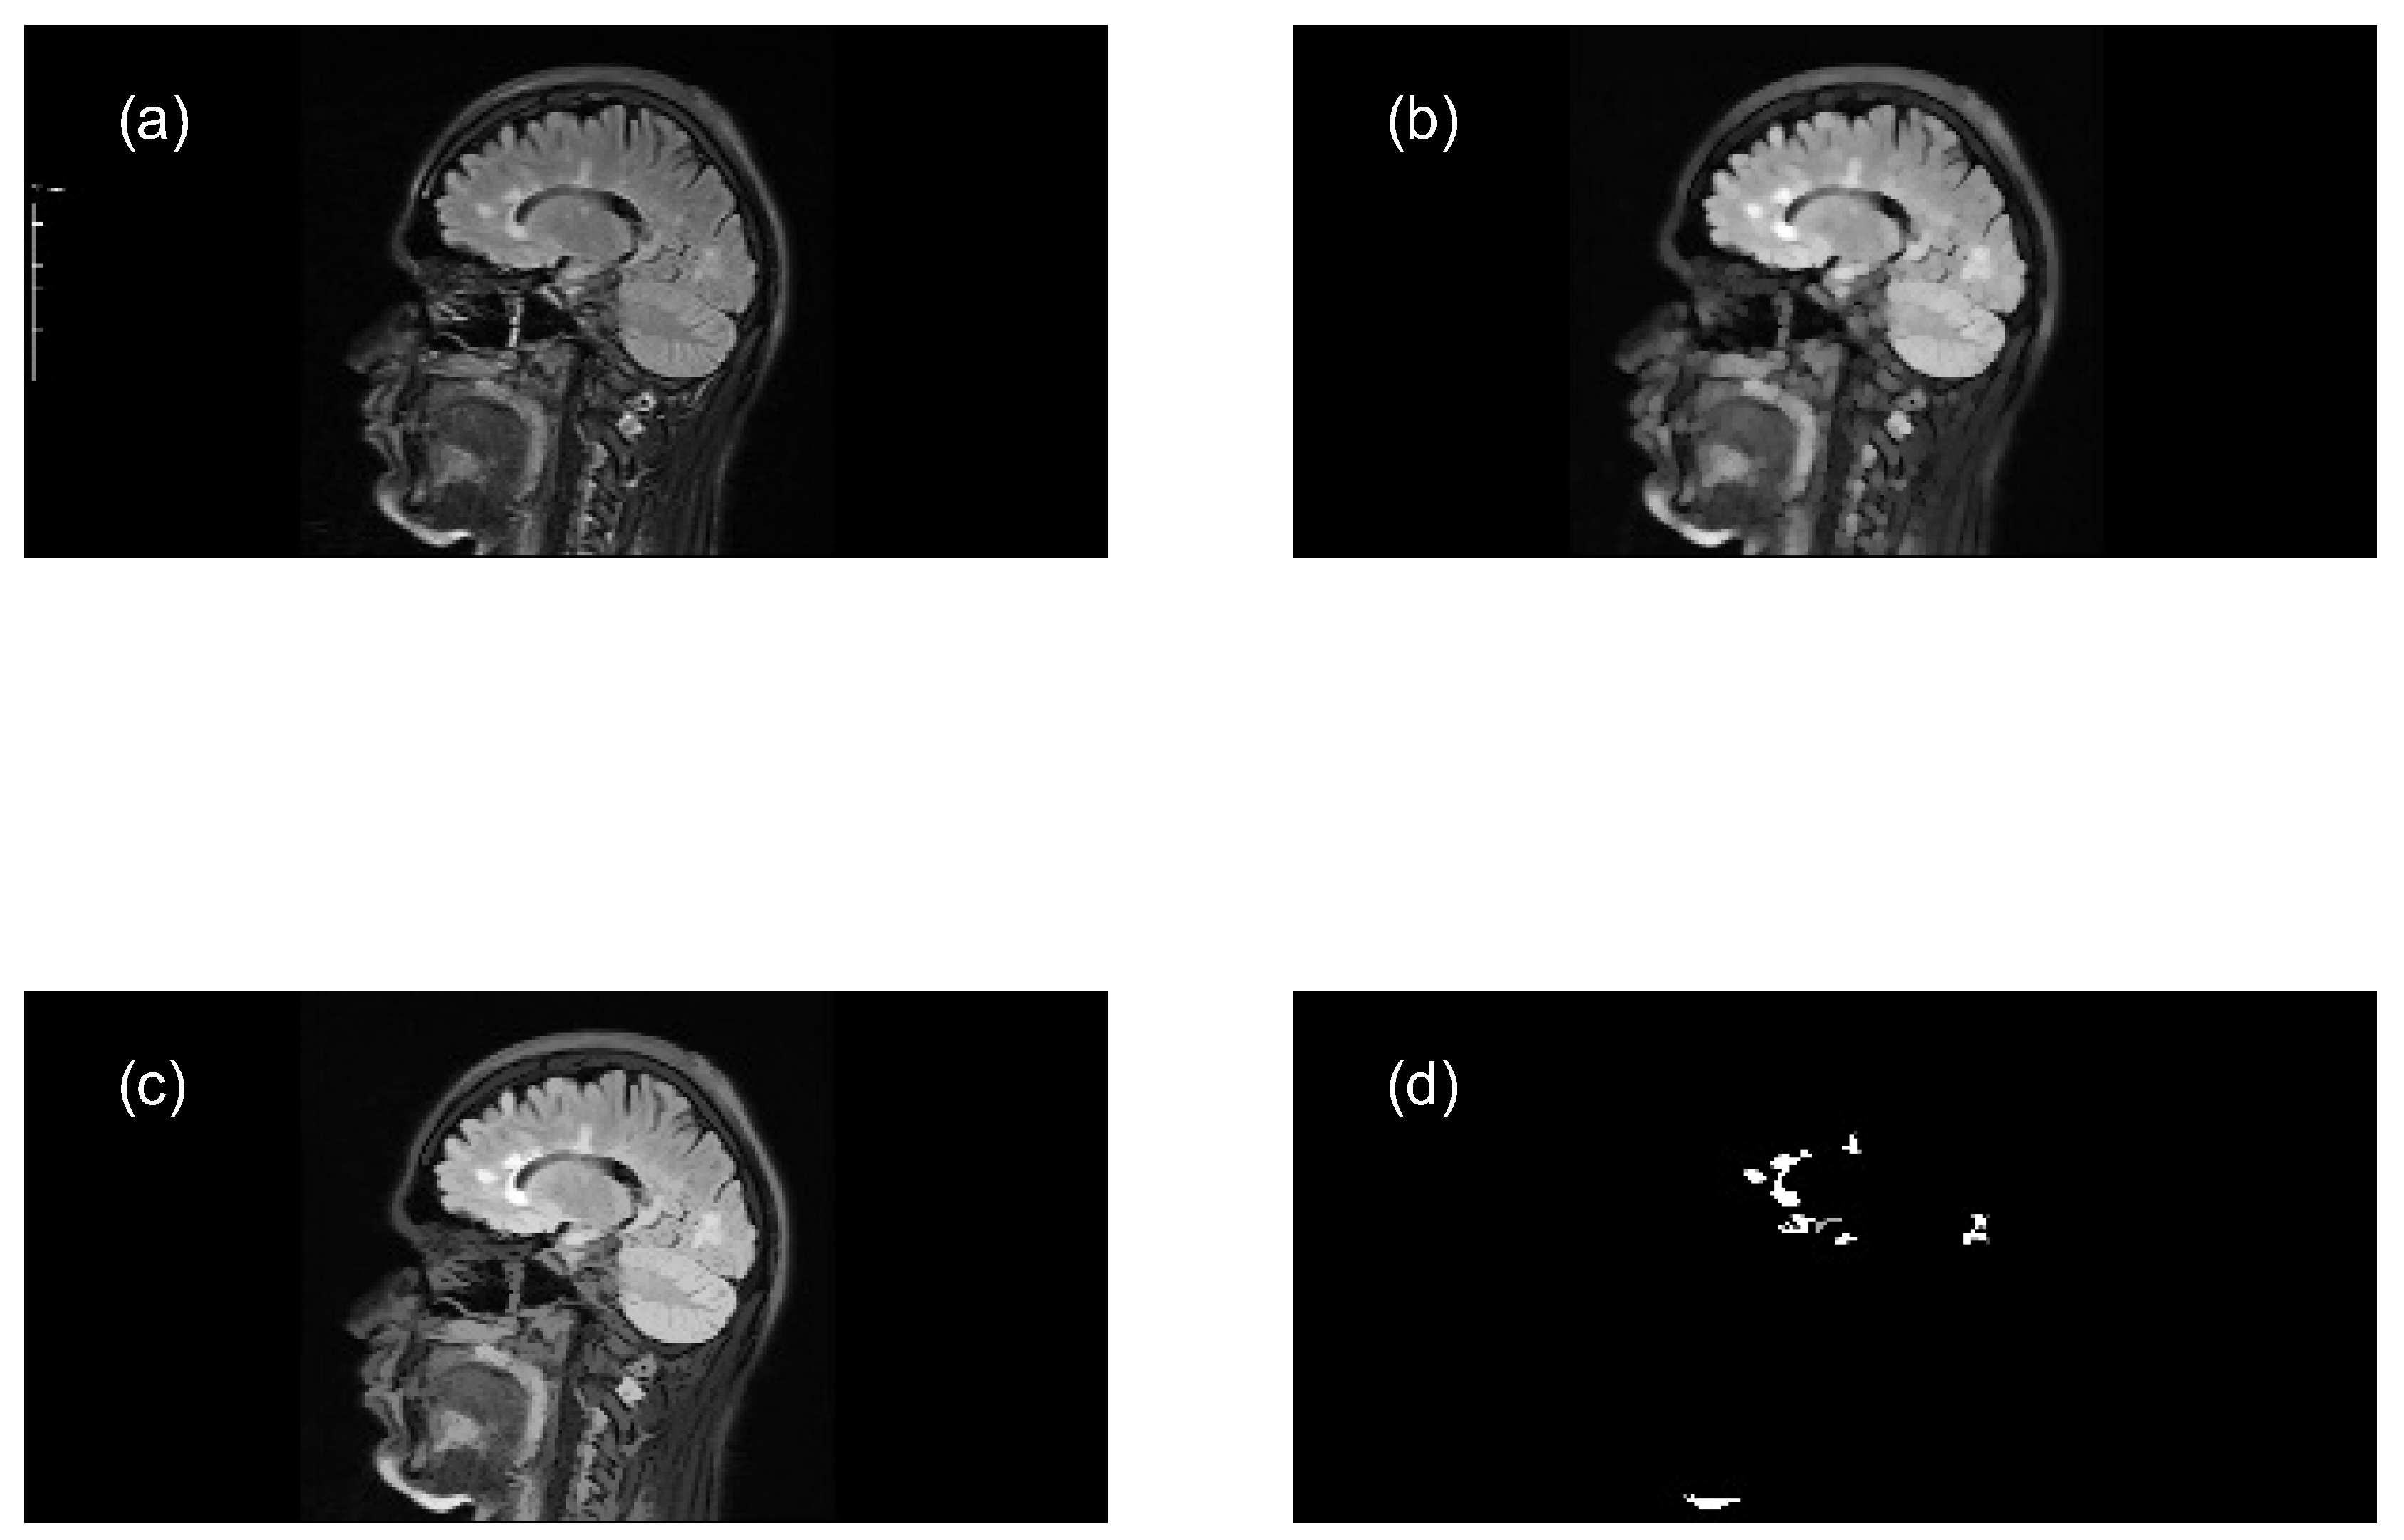

Perform opening morphological transformations on brain images of MS patients and healthy individuals (axial and sagittal MRI), compute the granulometry of objects (Equation 7), and use the resulting data to train two ANN models, applying the following steps:

- Read the original color image (.png) and convert it to grayscale (e.g. uint8 array 569x1158x3 → uint8 array 569x1158).

- Perform a morphological opening transformation on the image in grayscale (mask image) to create a marker image using a SE. This operation consists of an erosion followed by a dilation using the same SE. The created SE is disk-shaped with radius r, which matches the geometric properties of the relevant structures of a brain image.

- Perform an opening by reconstruction transformation on the mask image (Equation 5), using the marker image to identify high-intensity objects in the mask image.

- Adjust the intensity values of the opened image by reconstruction, which increases the contrast of the output image, to extract relevant structures (MS lesions).

- Compute the granulometry of objects of the opened image by reconstruction for different radius values () of the SE.